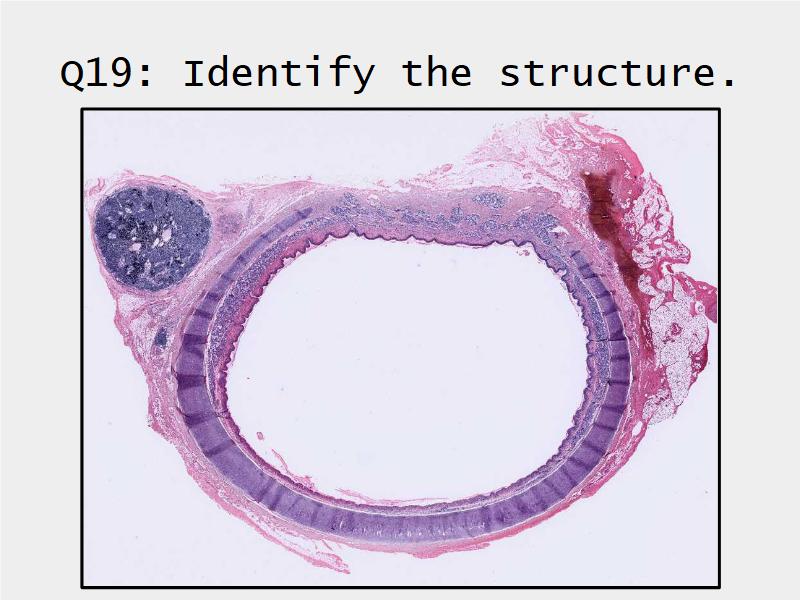

- Slide 73: Trachea

Respiratory epithelium

- Pseudostratified

- Ciliated

- Columnar

- Epithelium with

- 4 Cells

- Ciliated columnar cells

- Non-ciliated columnar cells

- Goblet cells

- Basal cells